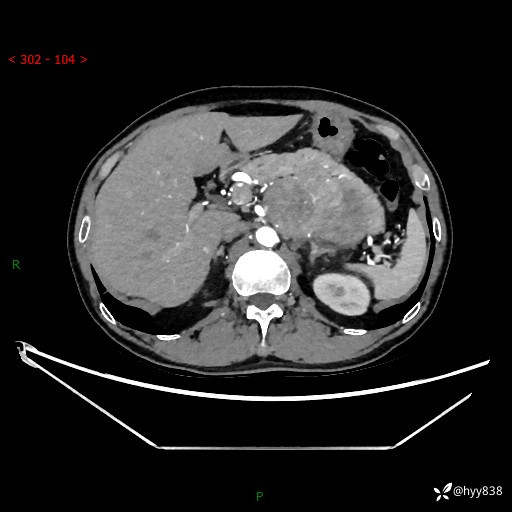

年龄:61岁

主诉:发现腹膜后肿瘤3天

腹部CT平扫+增强(动脉期+静脉期)